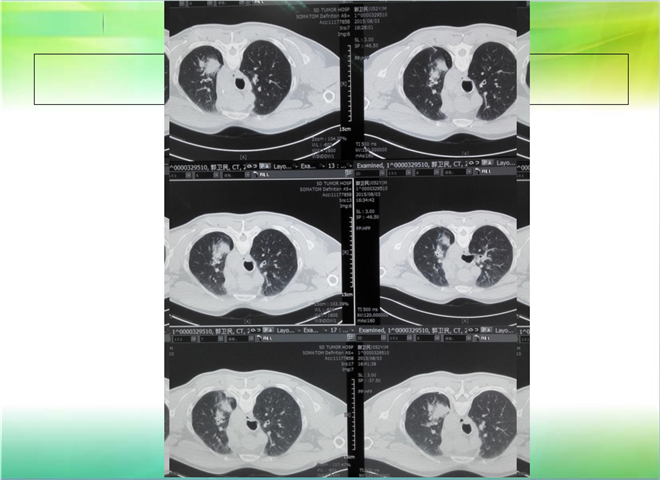

CT引导下穿刺活检术